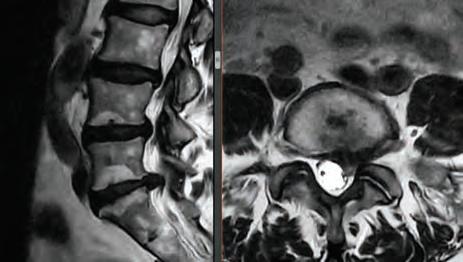

After explaining to Dr. Arakal what was going on, he performed a myriad of tests, and immediately sent her for an MRI. After reviewing the results, Dr. Arakal recommended surgery. “I was hoping to have surgery later in the summer, but Dr. Arakal explained that once you start to have

neurologic symptoms (numbness, tingling, weakness) you need to have surgery sooner than later,” explained Cheryl.

“I’ve had some neck pain and back pain that was manageable for years, although my right arm and hand had been getting weaker and weaker over time,” says Cheryl, who was also becoming increasingly prone to dropping things. She was getting Botox injections every eight weeks for migraine headaches, had balance issues and was known to fall. Hearing these details further cemented Dr. Arakal’s diagnosis for immediate neck surgery. In looking at the options available, Disc Replacement, which is a motion preservation surgery, was considered. However, it was determined she was not a candidate due to her physiology. Dr. Arakal then recommended a neck fusion surgery.

Her neck fusion required a 24-hour hospital stay and a six-week recovery period, before her back surgery. While the neck fusion alleviated the numbness and lack of strength in her hand and arm, her back surgery was becoming increasingly more urgent as she was losing the ability to use her right leg and walk. “My right leg under my knee felt too heavy to pick up when I tried to walk,” explained Cheryl.

When it came time to address her back, Dr. Arakal re-evaluated her completely and determined that while he could do a fusion on her back that wasn’t what she needed. “‘What you need,’ he said, ‘is an ultra-minimally invasive discectomy which is done endoscopically so that it doesn’t disrupt your tissue but more importantly so that it doesn’t disrupt your bone,’” details Cheryl. In this ultra-minimally invasive spine surgery, relief is generally immediate and it requires a very small incision.